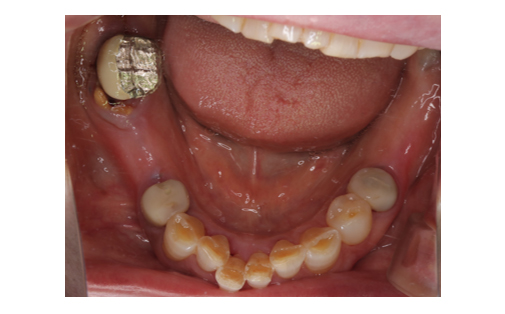

親知らずの歯を移植したケースです。患者様はとても喜ばれておりました。